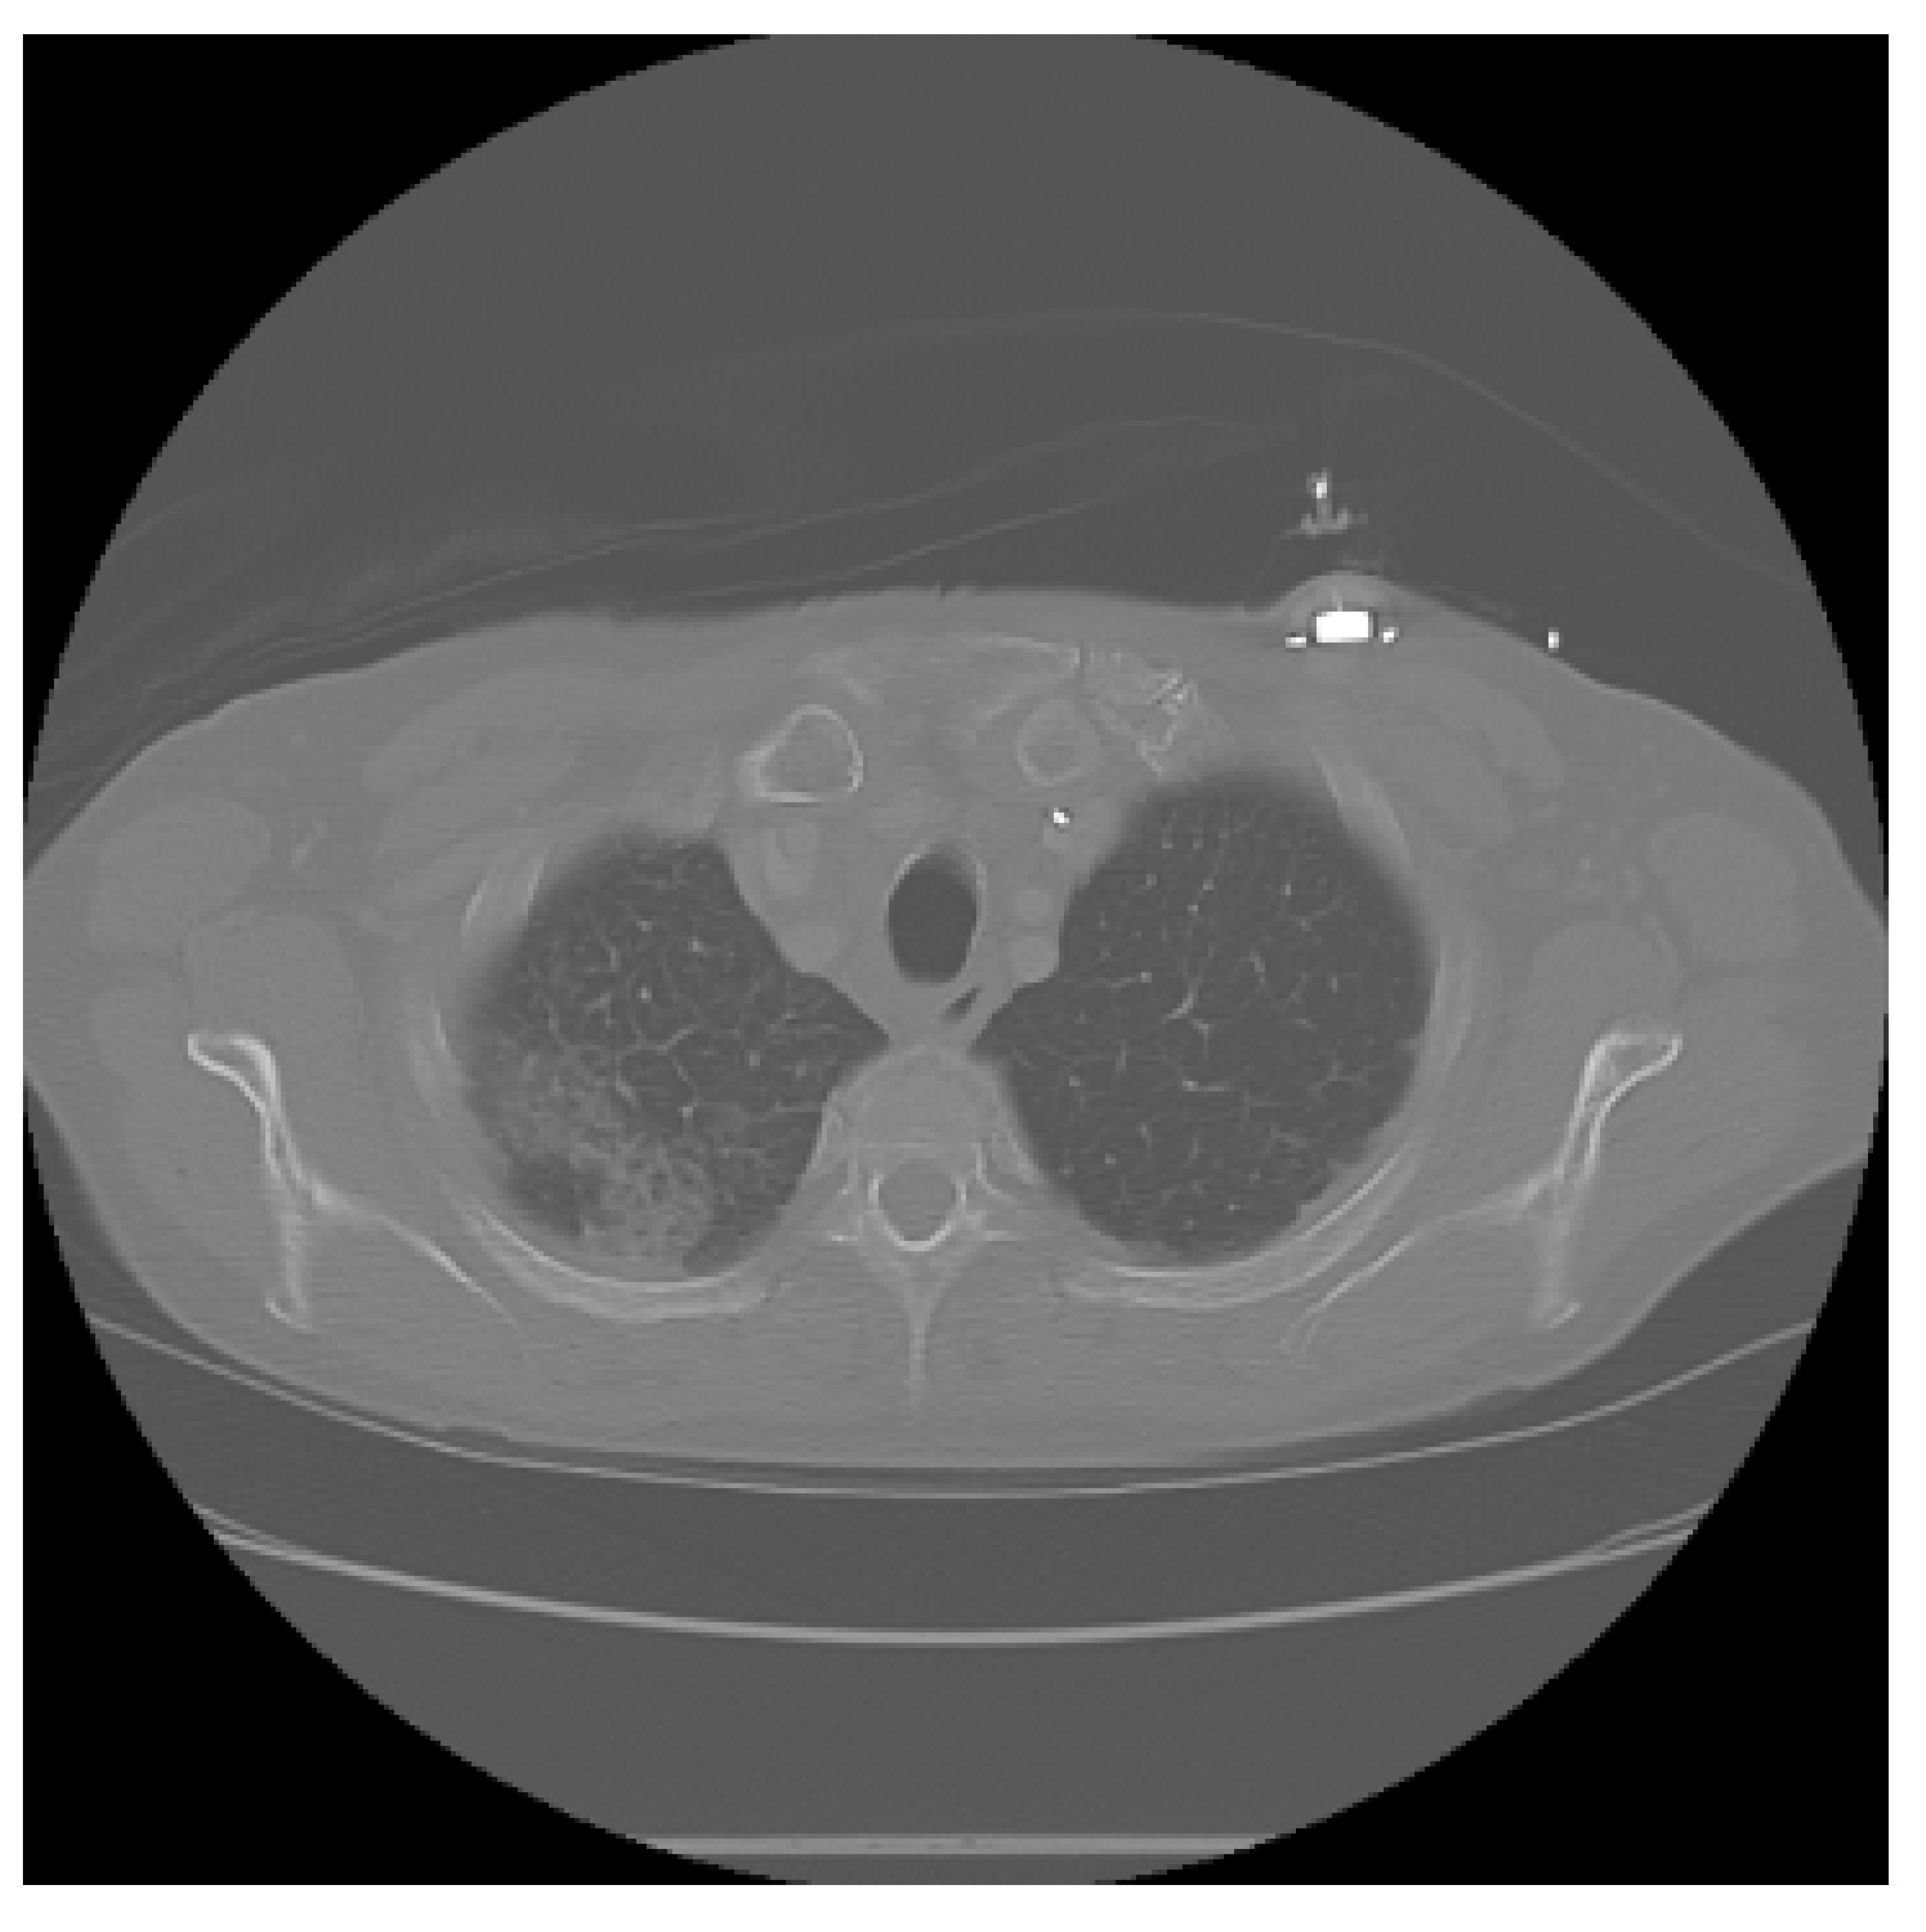

The APILungCancer interface provides intuitive functionality for loading and analyzing DICOM medical images. In the Load DICOM Images section, users can select and process CT scans for lung cancer evaluation. Once an image is loaded and analysis is performed, the software presents a visualization of the image along with the predicted probability of cancer (Table 7). Our study focused on lung cancer, including subtypes such as adenocarcinoma, squamous cell carcinoma, and small cell carcinoma. About 1000 training images and 300 test images from the CMB-LCA dataset were used to develop and validate the system.

In this example (Figure 5), the DICOM image 1-27.dcm from the test set was processed and the software calculated a cancer probability of 0.4267 (42.67%), indicating a high likelihood of malignancy.

Figure 5.

Determination of the probability of lung cancer. Example output of the system for the image 1-27.dcm, yielding a predicted probability of 42.67%, consistent with Table 7.

This value matches the result in Table 7, confirming the consistency of the predictions generated by the AI-based model integrated into the system.